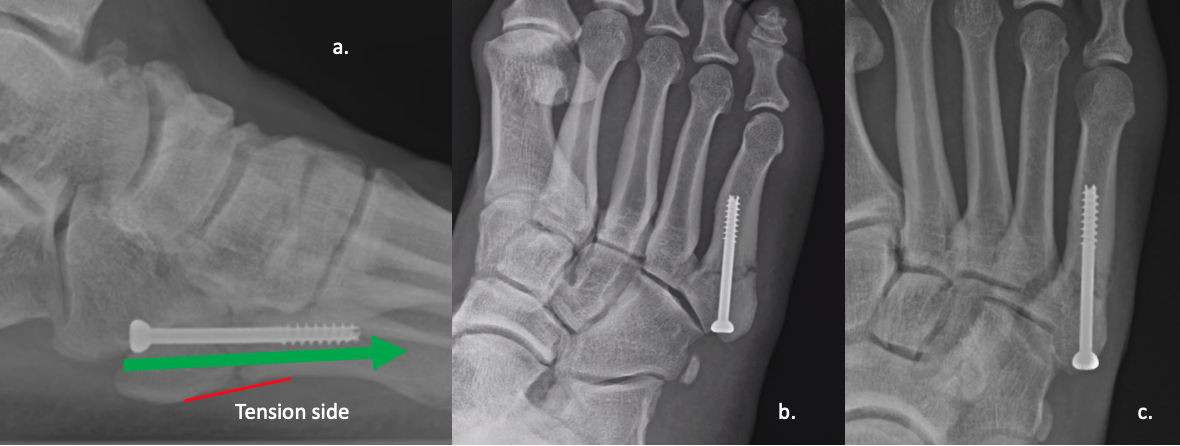

It is important to recognize the age of the fracture. I have noted radiologists routinely mistaking acute fractures for stress fractures based on location. I’ve heard surgeons tell patients that their fracture isn’t healing based on a 6-week-old injury, due to signs of bone resorption, which is normal sign of healing. Unfortunately, not all Jones fractures get X-rayed the same week, let alone within a month of the injury, so they may present already showing signs of radiographic healing. Either way, I find it is common that one may overread the imaging. See Figures 2-3.

Any screw utilized should have intramedullary purchase. Far too often in athletes, I find this does not happen. I also find screws of 4.5mm or greater are best, depending on the width of the metatarsal shaft. With digital radiology systems, surgeons can pre-plan and measure the canal in at least 2 views to ensure adequate intramedullary purchase. See Figure 4.